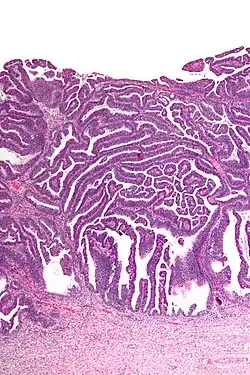

The name of the lesion describes it microscopic appearance. It has nipple-like structures with fibrovascular cores (papillae) that are long in relation to their width (villus-like), which are covered with a glandular pseudostratified columnar epithelium.

-

Very low magnification -